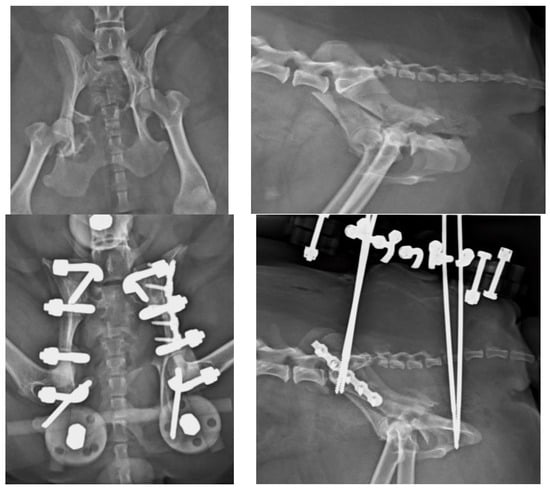

Figure 8. (Top left): VD view of a patient with fracture of the right ilium and of the right sacral articular process, and a left sacroiliac luxation. (Top right): Lateral projection of the same patient. (Bottom left): A combination of a type C EF and a plate have been used to stabilize the fractures. Note the lag screw for the left sacroiliac luxation. (Bottom right): Lateral projection of the same patient.